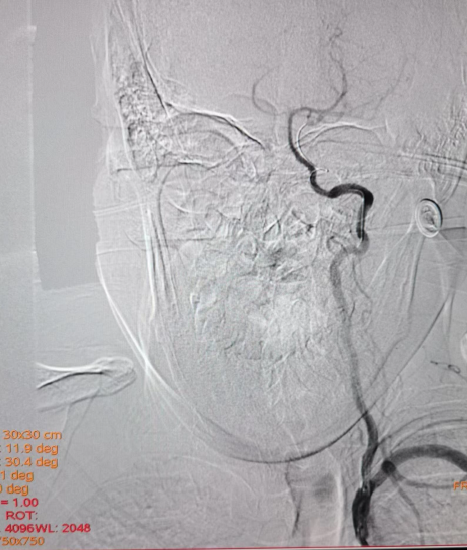

术前右侧椎动脉造影

病历夹什么径技·第152期|串联营病历夹:川陕大营_https://www.jmylbn.com_新闻资讯_第11张

病历夹什么径技·第152期|串联营病历夹:川陕大营_https://www.jmylbn.com_新闻资讯_第12张

病历夹什么径技·第152期|串联营病历夹:川陕大营_https://www.jmylbn.com_新闻资讯_第13张<<滑动查看下一张图片>>

术前左侧椎动脉造影

病历夹什么径技·第152期|串联营病历夹:川陕大营_https://www.jmylbn.com_新闻资讯_第14张

病历夹什么径技·第152期|串联营病历夹:川陕大营_https://www.jmylbn.com_新闻资讯_第15张

病历夹什么径技·第152期|串联营病历夹:川陕大营_https://www.jmylbn.com_新闻资讯_第16张

<<滑动查看下一张图片>>

左侧颈总动脉造影

病历夹什么径技·第152期|串联营病历夹:川陕大营_https://www.jmylbn.com_新闻资讯_第17张

右侧颈总动脉造影

病历夹什么径技·第152期|串联营病历夹:川陕大营_https://www.jmylbn.com_新闻资讯_第18张

病历夹什么径技·第152期|串联营病历夹:川陕大营_https://www.jmylbn.com_新闻资讯_第19张

病历夹什么径技·第152期|串联营病历夹:川陕大营_https://www.jmylbn.com_新闻资讯_第20张